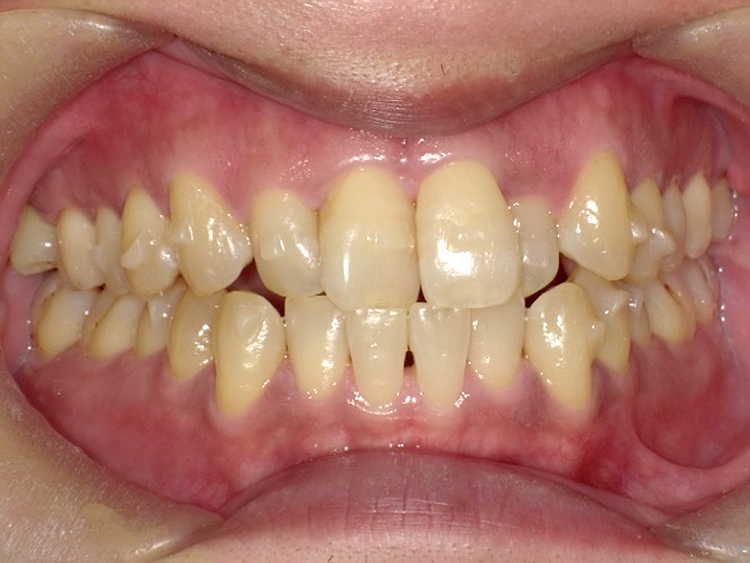

症例4

Before

After

| 主訴 | 上下前歯のがたつき |

|---|---|

| 年齢 | --- |

| 治療 期間 |

約9ヶ月 |

| 治療 内容 |

インビザラインiGoで上下顎の治療。 |

| 治療費 | ¥550,000(税込)/調整料含む |

| 治療のリスク | 矯正終了後は、リテーナーを指示通りに使用し、歯の後戻りを防ぐ必要があります。 |